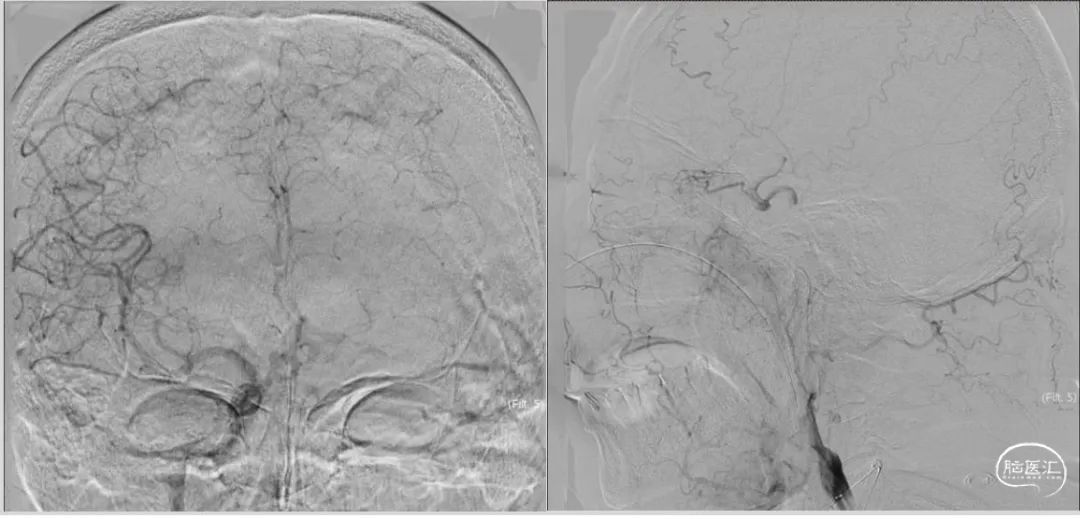

入院DSA:III型主动脉弓,后循环代偿不足,见图3,前交通动脉开放,左侧大脑前动脉通过软脑膜枝向左侧大脑中动脉供血区部分代偿,左侧颈内动脉起始部闭塞,左侧颈外动脉通过眼动脉向颈内动脉部分代偿,左侧大脑中动脉血栓形成,TICI分级0级,见图4。

图3.DSA造影:主动脉弓及左侧左侧椎动脉造影

图4.DSA造影:右侧颈内动脉正位及左侧颈内动脉侧位造影